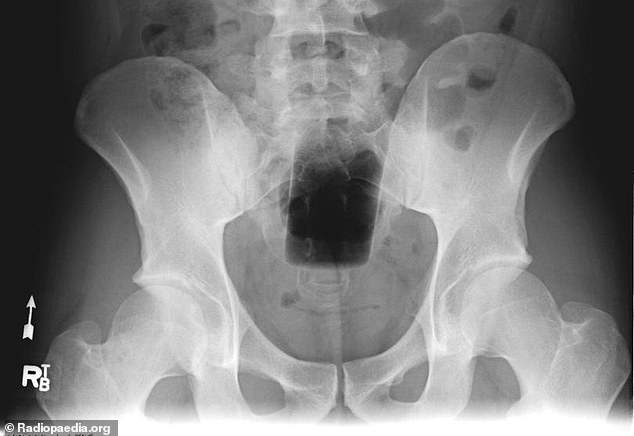

肛門

・鐵樂士那種噴罐

・折疊刀

・長超過15CM的玩具

・牙刷、牙籤

・吸污清潔棒

・兩支刀片

・按摩棒或震動棒~兩支

・避孕套包裝紙

・把粉塵吹開的噴嘴

・打火機

・水槍

・煮蛋計時器

・洗髮精罐子(各種尺寸)

・電燈泡

・聖誕節裝飾物

如果連鐵樂士或WD40那種罐子都可以塞,那有人挑戰保溫瓶什麼的我看也小case惹==